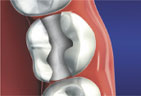

When decay has destroyed much of the tooth structure, a dental inlay or onlay may be recommended by Dr. Franziska Dutton or Dr. Daniel Cohen. Inlays and onlays are some of the strongest and most life-like dental restorations available.

Dental onlays and inlays in Redding, California, are applied much the same way we would for a standard filling, except that the tooth has been prepared by an impression and the onlay or inlay is designed out of a solid material instead of a filling composite. This offers increased strength and beauty.